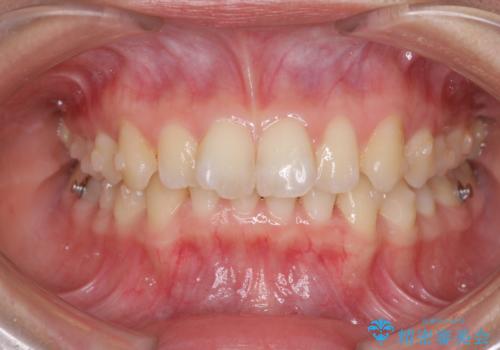

インビザラインによる前歯の矯正治療

- 口元の深い咬み合わせ(ディープバイト)を気にして来院された患者様です。

インビザラインによる上下歯列の遠心移動(後方移動)により、口元のデコボコとディープバイトを改善することとしました。

下顎左右の犬歯とその後ろにある第一小臼歯、計4歯がシミュレーション通りに動かずディープバイトがなかなか改善されませんでした。

マウスピースの再製作を何度か行いましたがうまくいかないため、部分的にワイヤー矯正を併用することを提案しました。しかし、最も気になっていた前歯のデコボコはきれいに改善されたため、これ以上治療を希望されず、治療を終了することとしました。(今後気になった際には再開する予定です)